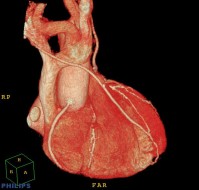

外来でできる検査(心電図,心エコー図,運動負荷心電図,ABI,冠動脈CT等)

| ▲マルチスライスCTによるバイパス手術後冠動脈造影 | ▲冠動脈の狭窄を検出します |